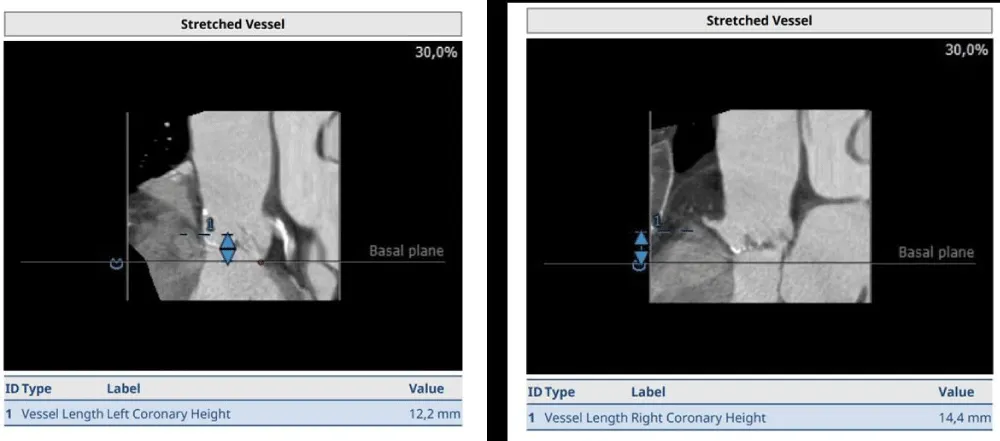

The clinical case concerns an 81-year-old woman with a history of systemic arterial hypertension, hypercholesterolemia, paroxysmal atrial fibrillation, chronic kidney disease, iron-deficiency anemia, and bilateral carotid atheromatosis for which she underwent a Carotid Endarterectomy (CEA) procedure. Additionally, she had a history of breast carcinoma, treated with surgery, subsequent chemotherapy, and ongoing Letrozole therapy. In 2019, the patient presented to the emergency department due to exertional dyspnea and low-threshold angina. During hospitalization, high average ventricular response (109 BPM) atrial fibrillation was diagnosed. Routine lab tests showed rising of hsTN-I (peak 800 pg/dL) and pro-BNP (peak 2476 pg/mL) and anemia Hb 9.1 g/dL. Echocardiography revealed severe depression of the left ventricular function (ejection fraction of 30%, with antero-apical akinesia) and low-flow-low-gradient aortic stenosis (mean gradient of 26 mmHg and AVAi of 0.5 cmq/m2 and SVi 29 mL/m2). So it was performed a Dobutamine stress Echo showed a rise of SVi up to 38 mL/m2 and a mean aortic gradient of up to 48 mmHg. Coronary angiography showed the right dominant coronary artery, of good caliber and course, with no angiographically significant lesions (Figure 1). The Left Main artery, with good caliber, had a 90% calcific stenosis at the distal segment, involving the proximal segment of the Left Anterior Descending artery. The Left Circumflex artery, with good caliber and course, presented a 30% ostial stenosis. The Intermediate Branch, with good caliber and course, showed 80% stenosis at the proximal segment (Figure 2). The Left Anterior Descending artery, also of good caliber and course, was diffusely atherosclerotic with a long, severely calcific 80% stenosis at the mid-distal segment (Figure 3). Therefore, the case was discussed by a multidisciplinary Heart team at our center. The STS score calculated indicated a mortality risk of 11.4%. Due to this high risk, surgical treatment was not considered, and the patient underwent a four-step percutaneous intervention. Before the intervention, a CT angiography was performed, revealing an aortic annulus area of 433.2 mm2, a perimeter of 75.3 mm, and a coronary height from the annulus of 10 mm. The right common femoral artery mean diameter was 6.1 mm2 and the external iliac artery was 8.4 mm2 with moderate tortuosity without significant calcification (Figure 4-6). Therefore, a 23 mm Edwards Sapien 3 valve was chosen. Our strategy consisted of 4 steps:

Figure 4: Before the intervention, a CT angiography was performed, revealing an aortic annulus area of 433.2 mm2, a perimeter of 75.3 mm, and a coronary height from the annulus of 10 mm. Therefore, a 23 mm Edwards Sapien 3 valve was chosen.

Download Image

Figure 5: CT angiographic visualization of the vascular access route, displaying the right common femoral artery with a mean diameter of 6.1 mm^2 and the external iliac artery at 8.4 mm^2. Moderate tortuosity without significant calcification is noted, aiding in the strategic planning of vascular access for the percutaneous intervention.

Figure 6: An image detailing the absence of significant calcification in the patient’s vascular access pathway, further elaborating on the favorable anatomical conditions for the percutaneous approach. This image complements the data presented in Figure 5 by highlighting the minimal calcific burden, which facilitates the procedural planning and execution of the transcatheter interventions.